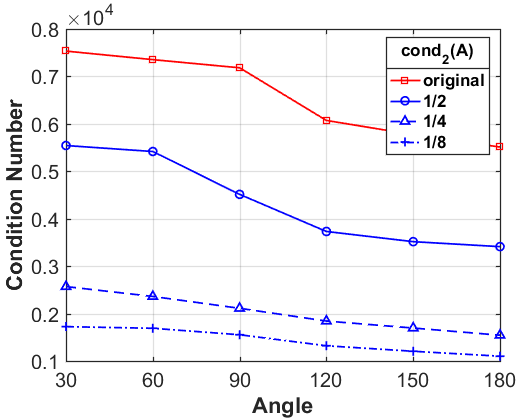

where denotes the number of angles in the angular interval for limited-angle CT reconstruction, denotes the number of units on the detector, and represents the number of pixels of the input image. For CT reconstruction problem (1), the condition number of the system matrix directly affects the stability of the solution [37]. The larger the condition number of the system matrix, the more serious the ill-posedness of the inverse problem, which may result in the degradation of the numerical methods.

Let us define a low-resolution system matrix , the geometric parameters of which are consistent with the system matrix , i.e., and of being the same as , and only the number of the pixels changes. More specifically, we use the equidistant sampling with the down-sampling rate . Then the dimension of the low-resolution system matrix becomes , and the low-resolution image can be expressed by the down-sampling matrix as given below

where is the down-sampled image and is a diagonal matrix with diagonal elements being either 1 or 0. Then we can arrive at the main theorem supporting our observation that a low-resolution problem has better numerical stability.

Next, we numerically compare the condition numbers of the system matrices for both the low-resolution and original reconstruction problems by 1-norm, 2-norm and -norm, respectively. As shown in Fig. 8, we can observe that the condition numbers of the low-resolution reconstruction problem are much smaller than the original reconstruction problems for different scanning angles, which are consistent with our theoretical analysis. In fact, larger condition numbers allow for undesired solutions, which also numerically satisfy the forward model (1). More importantly, the constraint in our model (2) can help to find better solution from the null space, which has already been perfectly demonstrated by our numerical experiments.

What is more, as shown in Table III, IV and V, the smaller the down-sampling rate, the better the reconstruction result. Since the quality of the image prior decreases as the resolution decreases for the limited-angle reconstruction problems, there is a trade-off between the resolution and the quality. Thus, we track the relationship between the resolution of the low-resolution image priors and the performance of our LRIP-net. As shown in Fig. 9, the best reconstruction results are obtained using the low-resolution image prior with down-sampling rate . Although the smaller the condition number of the system matrix, the better the numerical stability of the solution, it does not mean that the better the performance of our LRIP-net.